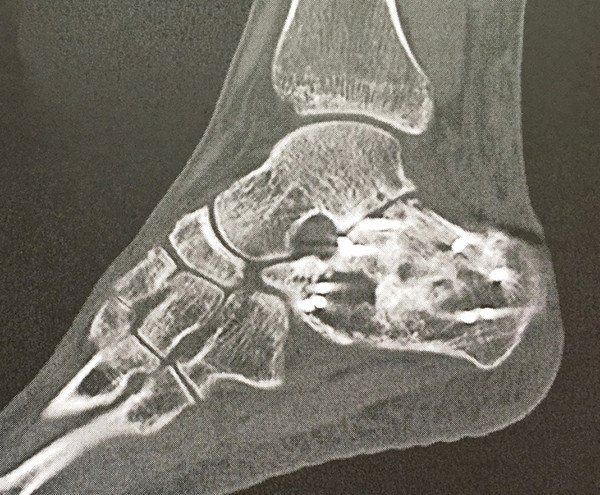

Da auf den Aufnahmen der Computertomografie (Abb. 4) bereits eine – durch die Fraktur bedingte – schwere Arthrose zwischen Sprung- und Fersenbein, welche gemeinsam das untere Sprunggelenk bilden, nachweisbar war, sahen wir eine alleinige Entfernung des Osteosynthesematerials als nicht erfolgsversprechend an und empfahlen der Patientin zusätzlich eine Versteifung dieses Gelenkes. Hierbei kommt es lediglich zu einer geringen Funktionseinbusse des Fusses und ist die einzige sinnvolle Option bei einer posttraumatischen Arthrose in diesem Bereich.

Nach einer kurzen Bedenkzeit willigte die Patientin ein, Abbildung 5 zeigt das postoperative Ergebnis. Die Nachbehandlung wurde unter Anlage einer Unterschenkel-Orthese durchgeführt, mit welcher für einen Zeitraum von 6 Wochen lediglich eine Teilbelastung an Unterarmgehstützen erlaubt war.

Unter physiotherapeutischer Anleitung erfolgte der schrittweise Belastungsaufbau, bereits 5 Monate nach dem Eingriff war die Patientin wieder uneingeschränkt im Alltag mobilisiert und zu 100% arbeitsfähig.

Als wir die Patientin das letzte Mal sahen, war ein Jahr nach der Versteifungsoperation vergangen. Sie konnte wieder schmerzfrei ihren Alltagsaktivitäten nachgehen und berichtete, dass sie nun «ein komplett neues Leben» habe.